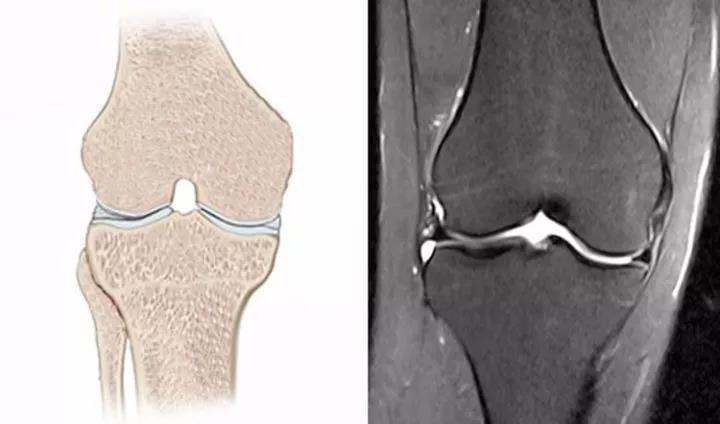

- 💪 关节/骨骼轴位

- 颈椎:0°-45°

- 腰椎:5°-15°1

超出范围可能提示炎症或结构异常。⚠️ 二、常见误区澄清

- 关节疼痛者:轴位偏移伴活动受限1